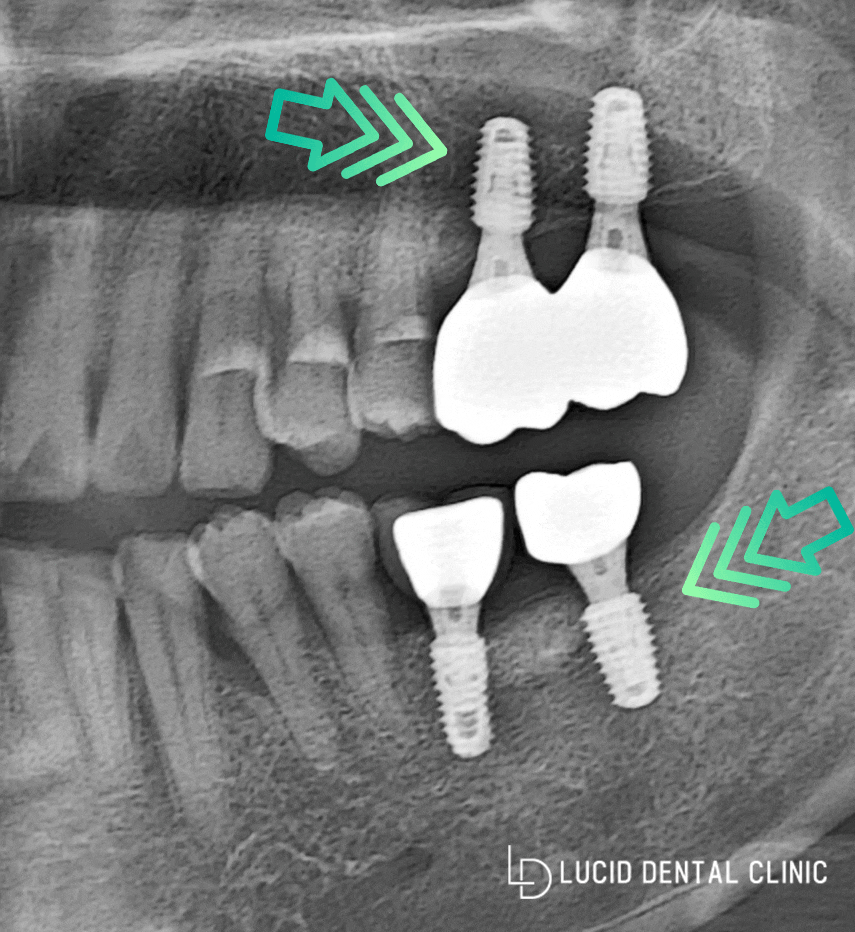

- 최종 결과

정밀 진단 및 검사 결과에 맞춰서

임플란트 수술을 완료했습니다.

큰 문제없이 잘 심어졌으며,

교합 또한 꼼꼼하게 체크하여

위아래 서로 잘 맞물릴 수 있도록

조정해드렸습니다.

환자분 역시 이전에 없었을 때와 다르게

이가 서로 맞닿고 있는게 너무 좋다며,

조금 더 빠르게 할걸 그랬다는 말씀을 주셨습니다.